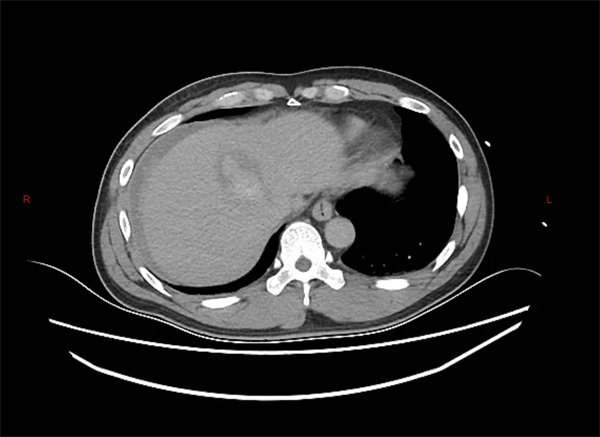

患者为一名中年男性,在工作时不慎被重物砸伤腹部,被紧急送至宝鸡市人民医院急诊科。入院时,患者面色苍白,心率快,腹部有压痛,急诊团队立即为其安排了腹部平扫CT检查。初步CT结果显示:腹腔内存在积血,盆腔有血肿形成,但令人困惑的是,并未发现明显的肝脾破裂直接征象。

通常情况下,肝脾破裂在CT影像上会有相对明确的表现,但此患者的初步影像却呈现“隐匿性”特点。面对这一情况,肝胆胰脾外科主任金上博立即组织科室进行紧急讨论,仔细分析患者伤情与CT影像后,高度怀疑存在活动性出血,且源头很可能就在肝脏。

“虽然平扫CT未见典型破裂征象,但腹腔积血和患者生命体征的变化提示我们,必须进一步明确出血来源。”主管医生在讨论中表示。科室团队当机立断,决定为患者进行急诊增强CT检查。

增强CT犹如为医生装上了“透视眼”,通过对比剂的动态分布,清晰揭示了隐藏在正常肝组织下的破裂伤——患者的肝脏确实存在裂伤,且位置较为隐蔽。这一关键诊断成为后续精准治疗的基础。